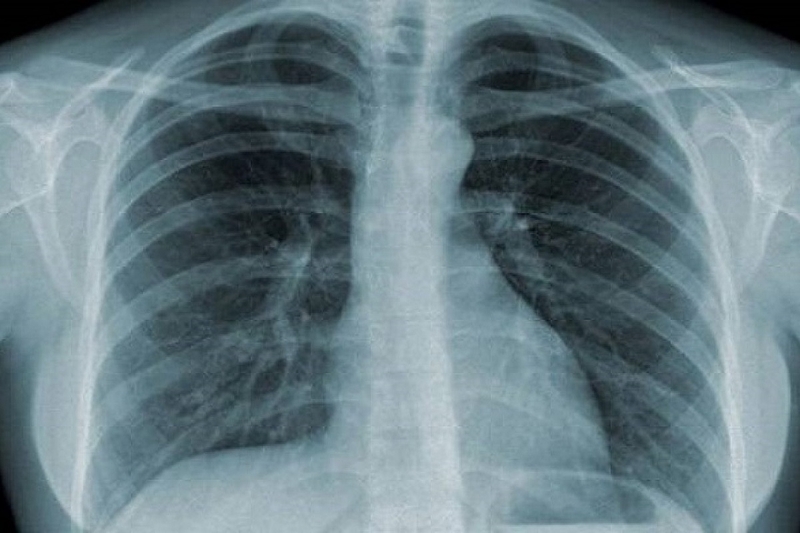

X quang

X quang không phải phương pháp dùng để chẩn đoán bệnh phế quản, tuy nhiên dùng để phân biệt với các bệnh lý thuộc nhu mô phổi và màng phổi. X quang có thể bình thường hay thấy hội chứng phế quản với những hình ảnh sau:

• Hình ảnh dày thành phế quản: Thấy các phế quản phân thùy (đường kính từ 3 - 7mm) có hiện tượng dày lên, có thể thấy hình ảnh đường ray xe điện hay hình nhẫn.

• Hình ảnh các mạch máu tăng đậm ở cả 2 bên trường phổi.

• Các hình ảnh trên có thể phối hợp với nhau, kèm theo viêm phổi bội nhiễm tạo nên hình ảnh phổi bẩn, thường gặp trong bệnh phổi tắc nghẽn mạn tính.

Hội chứng phế quản là gì? Nguyên nhân và triệu chứng thường gặp trong hội chứng phế quản X quang giúp chẩn đoán phân biệt bệnh phế quản với bệnh lý khác tại phổi